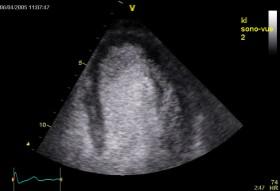

Echokardiografie: LEVÁ KOMORA bez dilatace a hypertrofie, s normální systolickou funkcí a regionální kinetikou kromě D shape, EF LK 55-60%. Diastolická funkce: porucha relaxace LK. PRAVÁ KOMORA FAC PK 18%, TAPSE 13 mm, Vt 9 cm/s, dilatace a hypertrofie PK, těžká prekapilární PH, odhadovaný PASP 90 mmHg, MPAP 55 mmHg, malý perikardiální výpotek

Echokardiografie: LEVÁ KOMORA bez dilatace a hypertrofie, s normální systolickou funkcí a regionální kinetikou kromě D shape, EF LK 55-60%. Diastolická funkce: porucha relaxace LK. PRAVÁ KOMORA FAC PK 19%, TAPSE 17 mm, Vt 9 cm/s, dilatace a hypertrofie PK, těžká prekapilární PH, odhadovaný PASP 130

mmHg, perikardiální výpotek